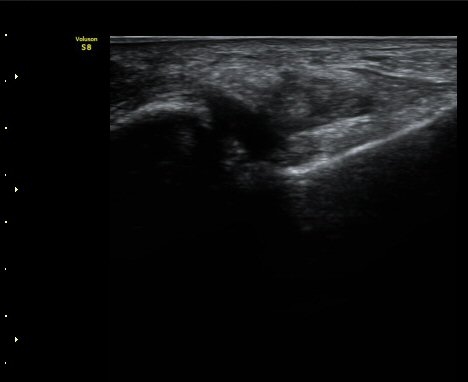

ÃÊÀ½ÆÄ°Ë»çÇÏ Àü°Å°ñºñ°ñÀÎ´ë ºÎÇϰ˻翡¼­ °Å°ñ°ú ºñ°ñ°£ ºÒ¾ÈÁ¤ÀÌ °üÂûµÈ´Ù(÷ºÎ µ¿¿µ»ó).

Á¤Áö »óÅÂÀÇ Àü°Å°ñºñ°ñÀδë ÃÊÀ½ÆÄ°Ë»ç¿¡¼­´Â ÀδëÀÇ Àú¿¡ÄÚ ºÎÁ¾ÀÌ °üÂûµÇ´Âµ¥

ÀÌ ¼Ò°ßÀ¸·Î´Â ÀÌ ÀδëÀÇ ±â´É ¼Ò½ÇÀ» È®ÀÎÇÒ ¼ö ¾ø´Ù.

±×·¯³ª ÃÊÀ½ÆÄ Åõ½ÃÇÏ ºÎÇϰ˻縦 ½ÃÇàÇÏ¸é °Å°ñ°ú ºñ°ñ»çÀÌÀÇ ¾ÈÁ¤¼ºÀÌ ÈѼյǾî

º¸´Ù Àû±ØÀûÀÎ Ä¡·á°¡ ÇÊ¿äÇÑ °ÍÀ¸·Î ÆÇ´ÜµÈ´Ù.